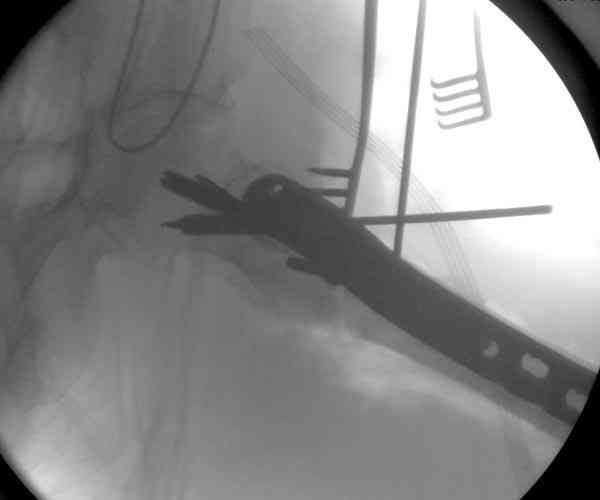

Адекватная фиксация достигается длинным 95 градусным Blade Plate, где клинок пластины, связывая головку со средней трети бедра, создал бы условия для сращения.

Другой вариант пластины, это Synthes Proximal Locking Plate предназначенный для лечения прксимальных переломов бедра, где три шурупа: два 7.3 мм, введенных в головку под углом 95, 120 и 5.0 мм в 130 градусов, создают угловую стабильность.

Профилактику прорезывания шурупов в кости можно добиться введением в отверстие цемента, потом проведением шурупа, цемент, застывая, удерживает шуруп в правильном положении.